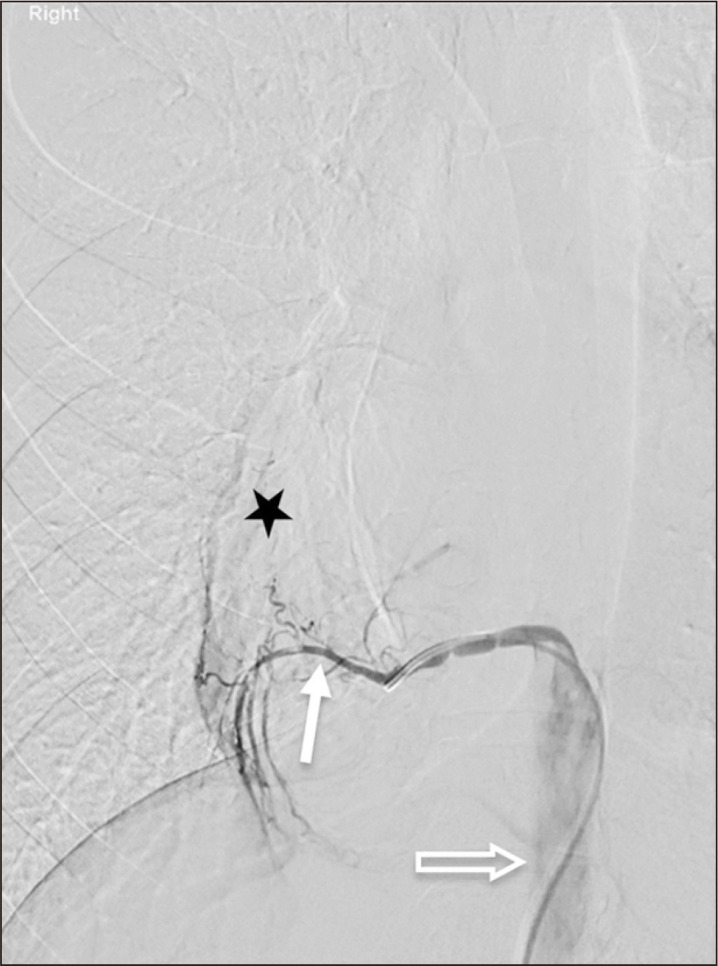

一位20岁出头的患者表现为咳嗽和炎症标志物升高。胸片显示右下区异常混浊。随后的计算机断层扫描显示右下叶脓肿,由主动脉产生的异常血管供血。这些发现与肺泡内隔离合并脓肿形成一致。患者接受抗生素治疗后出院,并计划在心胸外科医生的护理下进行选择性栓塞和肺叶切除术。一项文献综述显示,关于肺隔离的工作有限,很少有涉及类似表现的病例报告。因此,我们的病例是文献中罕见而重要的补充。

A patient in her early 20s presented with a cough and elevated inflammatory markers. A chest radiograph revealed an abnormal opacity in the right lower zone. Subsequent computed tomography showed an abscess in the right lower lobe that was fed by an anomalous vessel arising from the aorta. These findings were consistent with intralobar sequestration complicated by abscess formation. The patient was treated with antibiotics and discharged home, with plans for elective embolization and lobectomy under the care of the cardiothoracic surgeons. A literature review revealed a limited body of work on pulmonary sequestrations, with very few reported cases involving similar presentations. Thus, our case represents a rare and important addition to the literature.